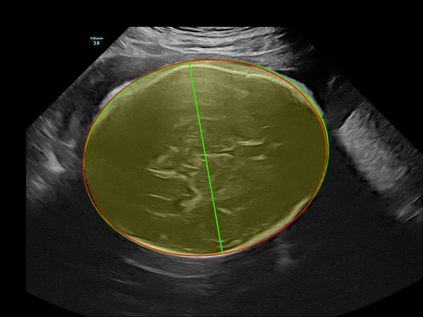

In this paper, we propose an end-to-end multi-task neural network called FetalNet with an attention mechanism and stacked module for spatio-temporal fetal ultrasound scan video analysis. Fetal biometric measurement is a standard examination during pregnancy used for the fetus growth monitoring and estimation of gestational age and fetal weight. The main goal in fetal ultrasound scan video analysis is to find proper standard planes to measure the fetal head, abdomen and femur. Due to natural high speckle noise and shadows in ultrasound data, medical expertise and sonographic experience are required to find the appropriate acquisition plane and perform accurate measurements of the fetus. In addition, existing computer-aided methods for fetal US biometric measurement address only one single image frame without considering temporal features. To address these shortcomings, we propose an end-to-end multi-task neural network for spatio-temporal ultrasound scan video analysis to simultaneously localize, classify and measure the fetal body parts. We propose a new encoder-decoder segmentation architecture that incorporates a classification branch. Additionally, we employ an attention mechanism with a stacked module to learn salient maps to suppress irrelevant US regions and efficient scan plane localization. We trained on the fetal ultrasound video comes from routine examinations of 700 different patients. Our method called FetalNet outperforms existing state-of-the-art methods in both classification and segmentation in fetal ultrasound video recordings.